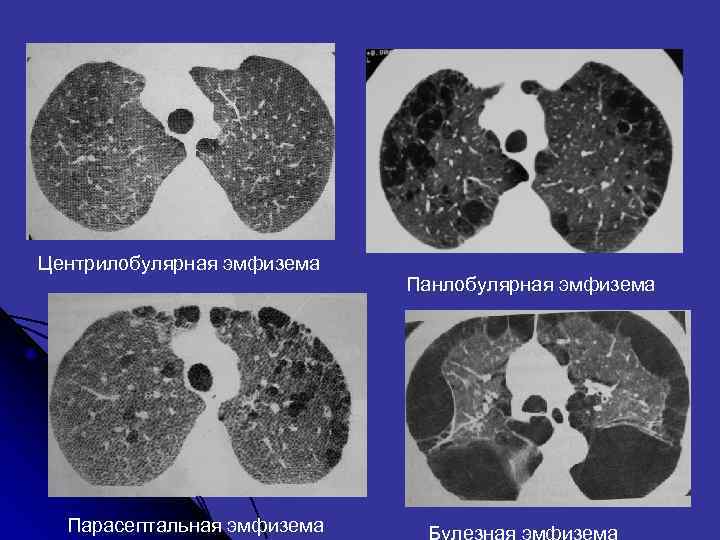

Морфологически выделяют три типа эмфиземы • Центрилобулярная (проксимальная ацинарная) • Панлобулярная (панацитарная) • Парасептальная (дистальная ацинарная)

Центрилобулярная (проксимальная ацинарная) - основной участок разрушения альвеол расположен вокруг терминальной бронхиолы, в центре вторичной легочной дольки Сотовое легкое - заключительная стадия хронических инфильтративных болезней легких, когда происходит замещение нормальной легочной ткани кистозными полостями. Подобные кистозные полости представляют собой расширенные респираторные бронхиолы.

Панлобулярная (панацитарная) – воздушные полости занимают целые ацинусы (дифицит альфа-1 -протеазы) Парасептальная (дистальная ацинарная) - развивается при вовлечениив процесс дистально расположенных ацинусов (молодые люди с рецидивирующими спонтанными пневмотораксами, ее развитие чаще всего связано с рубцовыми изменениями в легких )

Центрилобулярная эмфизема Панлобулярная эмфизема Парасептальная эмфизема Булезная эмфизема